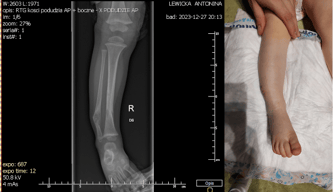

Dysplazja włóknista to rzadka choroba genetyczna, która dotyka tkanki łącznej. Objawia się ona nieprawidłowym wzrostem i rozmieszczeniem włókien kolagenowych w organizmie. W przypadku Antosi, ta choroba może ograniczać jej ruchliwość i sprawiać ból, co utrudnia jej codzienne funkcjonowanie.